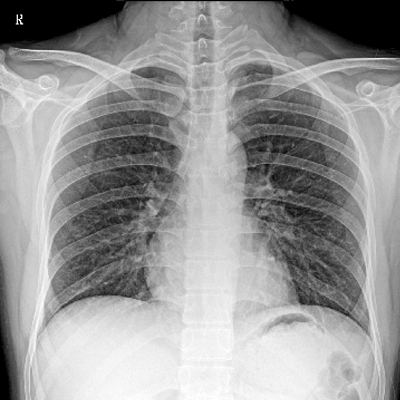

輕量化設(shè)計(jì) 小巧靈活 PLX5100

用于影像科、急診室、病房、ICU、手術(shù)室等多場(chǎng)景應(yīng)用。

● 數(shù)字化無(wú)線平板成像,操作簡(jiǎn)便,成像質(zhì)量高